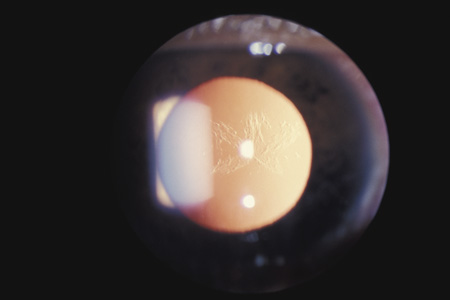

LENS

When the lens is struck by the cornea or by a strong shock wave, a transient anterior subcapsular cataract, known as a rosette cataract, may develop (Fig. 6). Repeated trauma, as in boxers, often causes posterior subcapsular cataract. Blunt trauma can also result in rupture of the anterior or posterior capsule.44,45 In severe cases, iridodonesis or a bead of vitreous in the anterior chamber signals a subluxed lens. Dislocation may also occur (Fig. 7). It is important to remember that ocular trauma is common, but lens dislocation is rare. Therefore, in patients with a dislocated lens, the clinician should always rule out predisposing causes such as Marfan's syndrome, homocystinuria and syphilis. In rare cases the lens itself can rupture and cause phacolytic glaucoma.

Fig. 6. An anterior subcapsular rosette cataract.